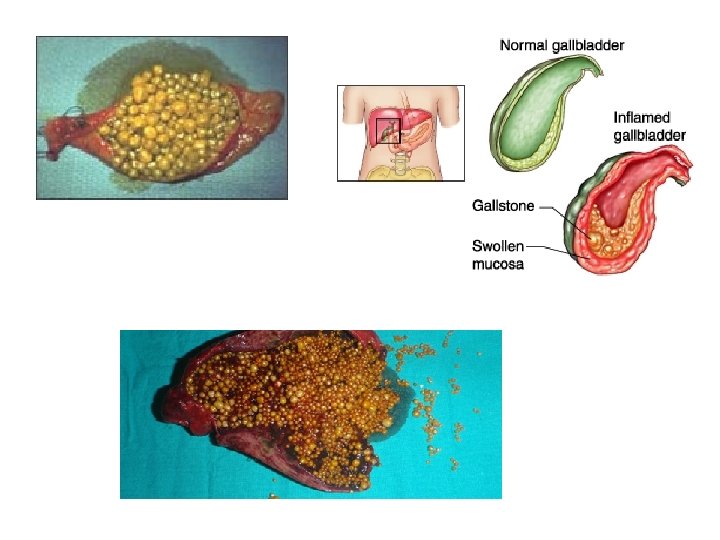

• ETIOLOGJIA: Mendohet se 90% e rasteve te kolecistitit vijne nga kalkuloza biliare. Te tjera: - bllokim i rrugeve biliare nga aderanca me organet fqinje, - periduodeniti, - ulcera peptike, - infiltrimi neoplazik. 10% jane nga shkaqe akalkuloze: brucelloza, ethja tifoide, mononukleoza infektive, salmonellozat etj.

KOLECISTITI AKUT: eshte inflamacioni akut i mureve te kolecistes (vezika e temthit) dhe me nje prirje te theksuar perkeqesimi duke krijuar gjendje serioze kercenuese per jeten e te semurit.